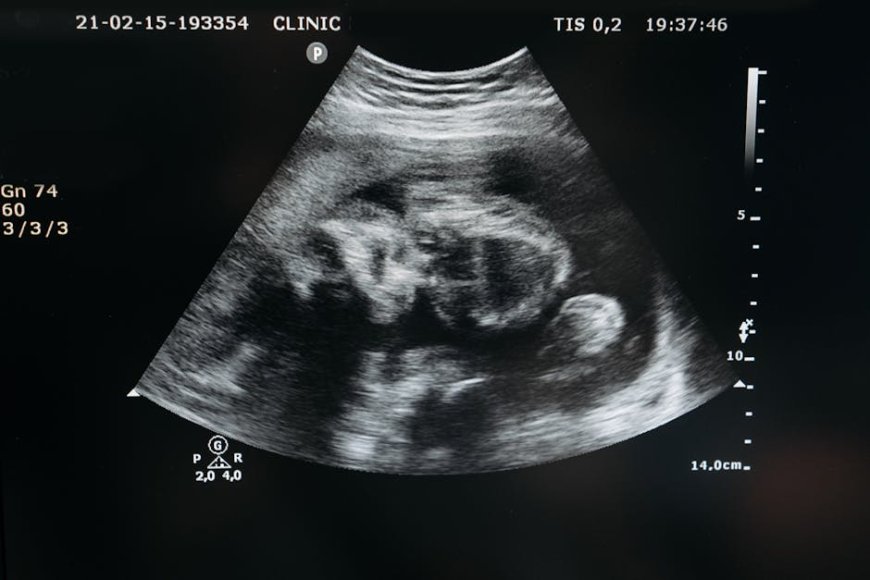

Dalam praktik klinis, ultrasonografi kehamilan berperan besar untuk memantau perkembangan janin, menilai parameter kehamilan, dan mendukung pengambilan keputusan medis.

Namun, kualitas hasil USG sangat dipengaruhi oleh beberapa faktor, termasuk posisi transduser, kualitas sinyal, serta pengalaman operator. AI pada sistem USG ditujukan untuk membantu konsistensi pemerolehan gambar dan mendukung interpretasi, sehingga potensi variasi antar operator dapat ditekan.